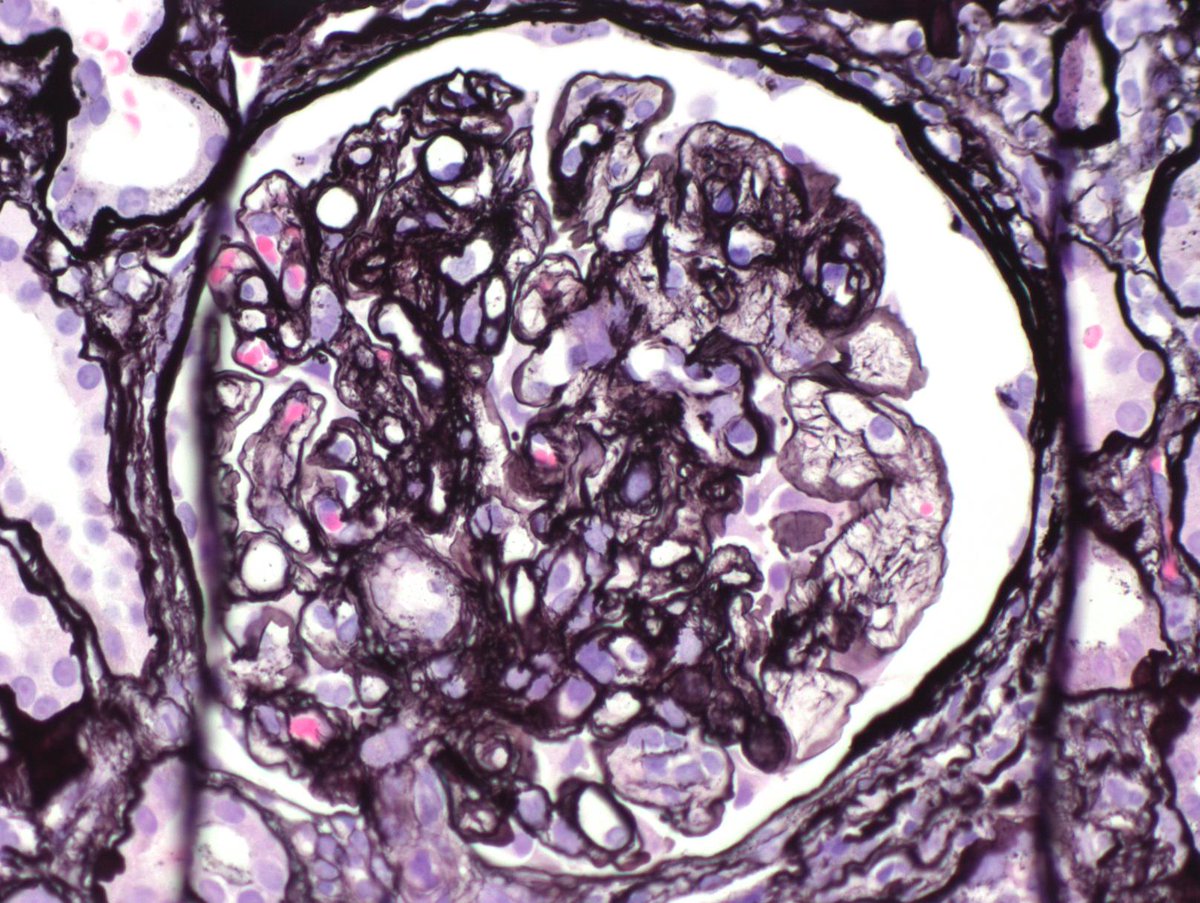

Long weekend often brings urgent cases. Here is one that was STATed, ended up showing anti-GBM GN. Diffuse crescents (nearly 100%). Linear IgG. #RenalPath